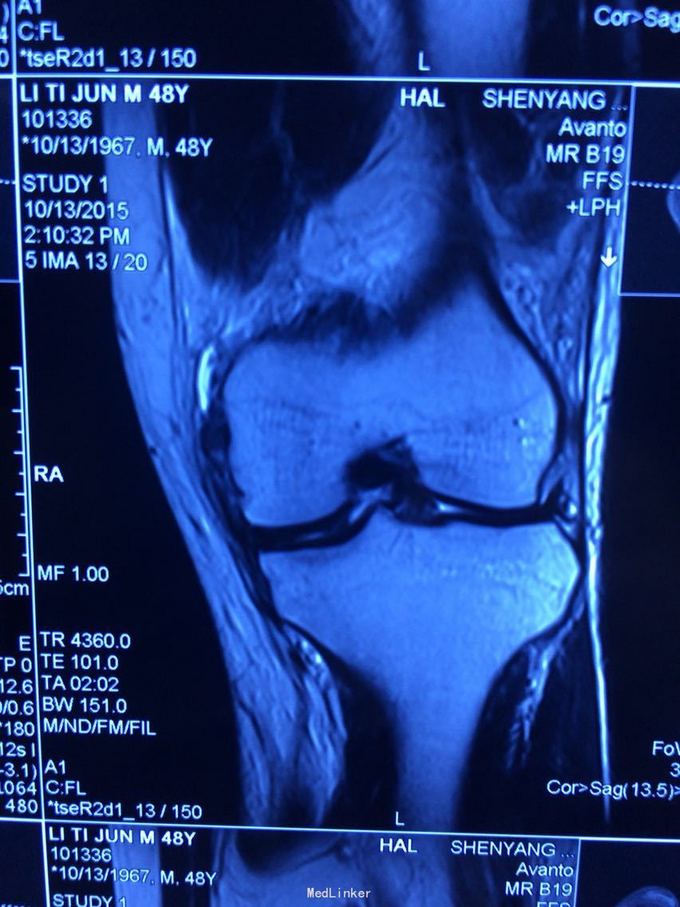

交通伤后膝关节疼痛,关节不稳。 患者交通伤,膝关节肿胀、疼痛,活动受限,肿胀消退后关节不稳。

查体:髌骨稳定,拉赫曼试验阴性,台阶征阳性3+,拨号征阴性,外翻0度阴性、30度阳性,内翻阴性。

诊断:膝关节多发韧带损伤,后交叉韧带、内侧副韧带 处理:给予关节镜下后交叉韧带重建,小切口修补内侧副韧带,取自体半腱股薄肌腱